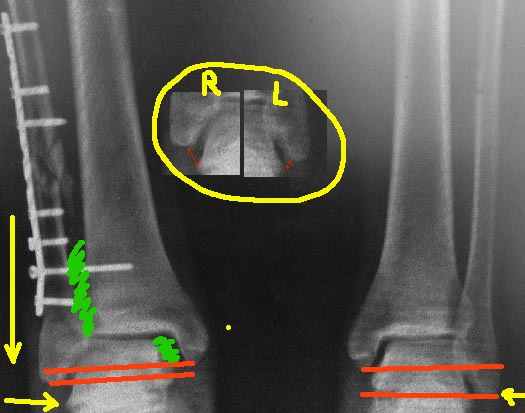

Я немного порисовал на вашем рентгенснимке, чтобы было понятно. теперь

несколько мыслей вслух.

1. Лодыжка укорочена, это видно на прямой проекции, особенно в

сравнении со здоровой ногой - красным нарисовано нормальное

соотношение длины лодыжек у данного пациента (на здоровой ноге) и

укорочение на оперированной. По центру картинки - фрагмент

рентген-снимка, где видно расстояние от верхушки наружной лодыжки до

таранной кости. На травмированной ноге оно значительно больше, за счет

укорочения. Поэтому:

2. Пластину убрать. Выполнить косую остеотомию, видимо на уровне

перелома, т.к. ниже малоберцовая кость будет наверняка фиксирована

рубцовыми тканями в межберцовой зоне, и выраженной подвижности вы не

получите.  Зачистить межберцовую зону, зайдя по переднему краю

малоберцовой кости (зеленое на картинке), убрать рубцовые ткани, чтобы

поставить лодыжку на место. Если есть необходимость, то сразу

выполнить доступ и с антеро-медиальной стороны, из небольшого разреза.

Зайдя за внутренюю лодыжку в сустав, вычистить весь фиброз оттуда

(зеленое на картинке), под контролем ЭОП убедиться, что руками

таранная кость легко прижимается к внутренней лодыжке. На ЭОПе

смотреть не ликвидацию подвывиха, а эффективность прижатия таранной

кости к внутр. лодыжке. Если не встает - значить не всё вычистили.

Лезьте снова.

3. После того, как все сегменты мобилизованы, межберцовая зона и

полость сустава у внутренней лодыжки очищены от фиброза, выполните

остеосинтез малоберцовой, с восстановлением её длины. Ориентироваться

можно по вырезке на таранной кости, соотношению её с внутренней

лодыжкой, а также по естественной ликвидации подвывиха стопы, без

грубых усилий.

Дельтовидную связку шить не вижу смысла.

Ну и на десерт, как фиксация достигнутого - межберцовый винт.